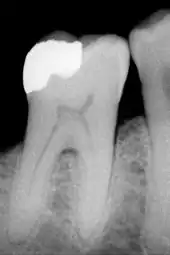

L'émail dentaire est une structure minéralisée d'origine épithéliale qui recouvre la couronne dentaire des vertébrés actuels et fossiles afin de la protéger des différentes agressions. L'amélogenèse (ou formation de l'émail) est assurée par les améloblastes (en), cellules sécrétrices qui sont détruites lors de l'éruption de la dent dans la cavité buccale. L'émail ne pouvant se régénérer en cas d'altération, il est doté par compensation d'une organisation tridimensionnelle complexe et d'un fort degré de minéralisation, qui en fait la structure la plus dure et la plus résistante de l'organisme, d'où son intérêt en médecine légale et en paléontologie. L'émail est la structure dentaire (et non le tissu car celui ci n'est pas vascularisé, ni innervé mais minéralisé, bien que très souvent même en clinique on parle de tissu amélaire)[1] normalement visible, supporté par une couche sous-jacente de dentine. Avec la dentine, le cément et la pulpe dentaire, il constitue un des quatre principaux tissus qui constituent la dent.

L'émail est composé de trois phases : la phase minérale représente 93-96 % en poids[2], la phase organique 0,4-5 %[3] et la phase aqueuse 3-7 % (le pourcentage d'eau étant en moyenne de 12 % pour la dentine et 33 % pour l'os)[4]. Sa partie minérale est principalement composée d'un réseau de cristaux d'hydroxyapatite (Ca10(PO4)6(OH)2). Le fort pourcentage de minéraux dans l'émail est responsable non seulement de sa rigidité et de sa dureté, supérieure à celle du tissu osseux, mais aussi de sa friabilité. La dentine, qui est moins minéralisée et moins friable, est indispensable comme support et compense les faiblesses de l'émail.

L'émail varie en épaisseur sur la surface de la dent. Il est plus épais au niveau du sommet de la couronne dentaire (plus de 2,5 mm) et plus mince sur la jonction émail-cément (JEC).

Structure

L'émail est la substance la plus dure du corps humain[7]. Il est surtout composé de phosphate de calcium et de carbonate de calcium, et il comprend moins de 1 % de matière organique[7]. Il a une organisation tridimensionnelle complexe, formée par la juxtaposition de structures élémentaires appelées cordons, bâtonnets ou prismes d'émail. Chaque prisme minéralisé de 4 à 8 µm de diamètre traverse l'émail, depuis la jonction émail-dentine jusqu'à la surface de la dent[8].

Ces prismes sont des cristaux d'hydroxyapatite entourés par une gaine de nature organique, imbriqués les uns dans les autres. En coupe transversale, ils ressemblent à un trou de serrure, avec la partie supérieure orientée vers la couronne de la dent et la base orientée vers la racine.